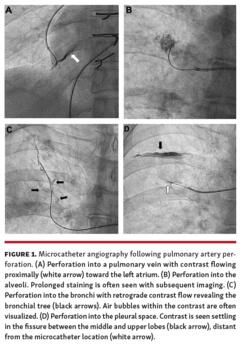

An antegrade true lumen to true lumen approach was attempted in all cases. We adhered to a wire-escalation technique utilized in the revascularization of chronically occluded coronary arteries3 with sequential upgrade of 0.014˝ coronary wires from spring coil to jacketed hydrophilic to high penetration power wires. Following wire penetration of the CTO cap, a microcatheter was advanced beyond the proximal occlusion and angiography through the microcatheter was performed. If an intraluminal position was confirmed, balloon angioplasty of the lesion was performed. Balloon dilations were performed using a maximum balloon diameter of 2.0 mm on vessels visually estimated between 2-3 mm in diameter, 4.0 mm on vessels between 4-5 mm in diameter, and 6.0 mm on vessels ≥6 mm in diameter. Balloon lengths ranged between 15-20 mm; however, serial dilations along the length of longer lesions were often required. No stents were implanted during any intervention. If angiography revealed an extravascular location, such as within the alveoli, bronchi, or pleural space (Figure 1), a wire was readvanced beyond the vascular perforation and the microcatheter was withdrawn. Balloon tamponade and/or heparin reversal were performed according to clinical need. If the microcatheter resided within the subintimal space, luminal re-entry was attempted.

Procedural complications were relatively common, occurring in 13 out of 21 interventions (Table 2). The vast majority were due to vessel perforation into either the alveoli, bronchi, pulmonary veins, or pleura. One patient experienced a retrograde PA dissection during 2 separate interventions on the same lesion. Angiography following each intervention demonstrated complete resolution of each dissection without apparent sequelae. Of the 12 cases of vessel perforation, 8 required no treatment whatsoever and had no impact on case duration. In 1 of these 8 cases, the patient experienced mild hemoptysis, which spontaneously resolved. Four cases of perforation required active management. Two of these perforations resulted in moderate hemoptysis. Of these, 1 patient received heparin reversal and balloon tamponade, successfully sealing the perforation; however, the procedure was terminated early, and the patient spent 1 extra day in the hospital for observation. The patient made a full recovery and went on to receive additional BPA. The remainder of the 3 perforations were treated with some combination of balloon tamponade and/or heparin reversal. Following hemostasis, heparin was rebolused and all 3 procedures resumed without further incident. There were no procedural complications in 7 interventions. Mild hemoptysis in the absence of angiographic evidence of vascular injury occurred in 2 of these cases, both of which resolved spontaneously.